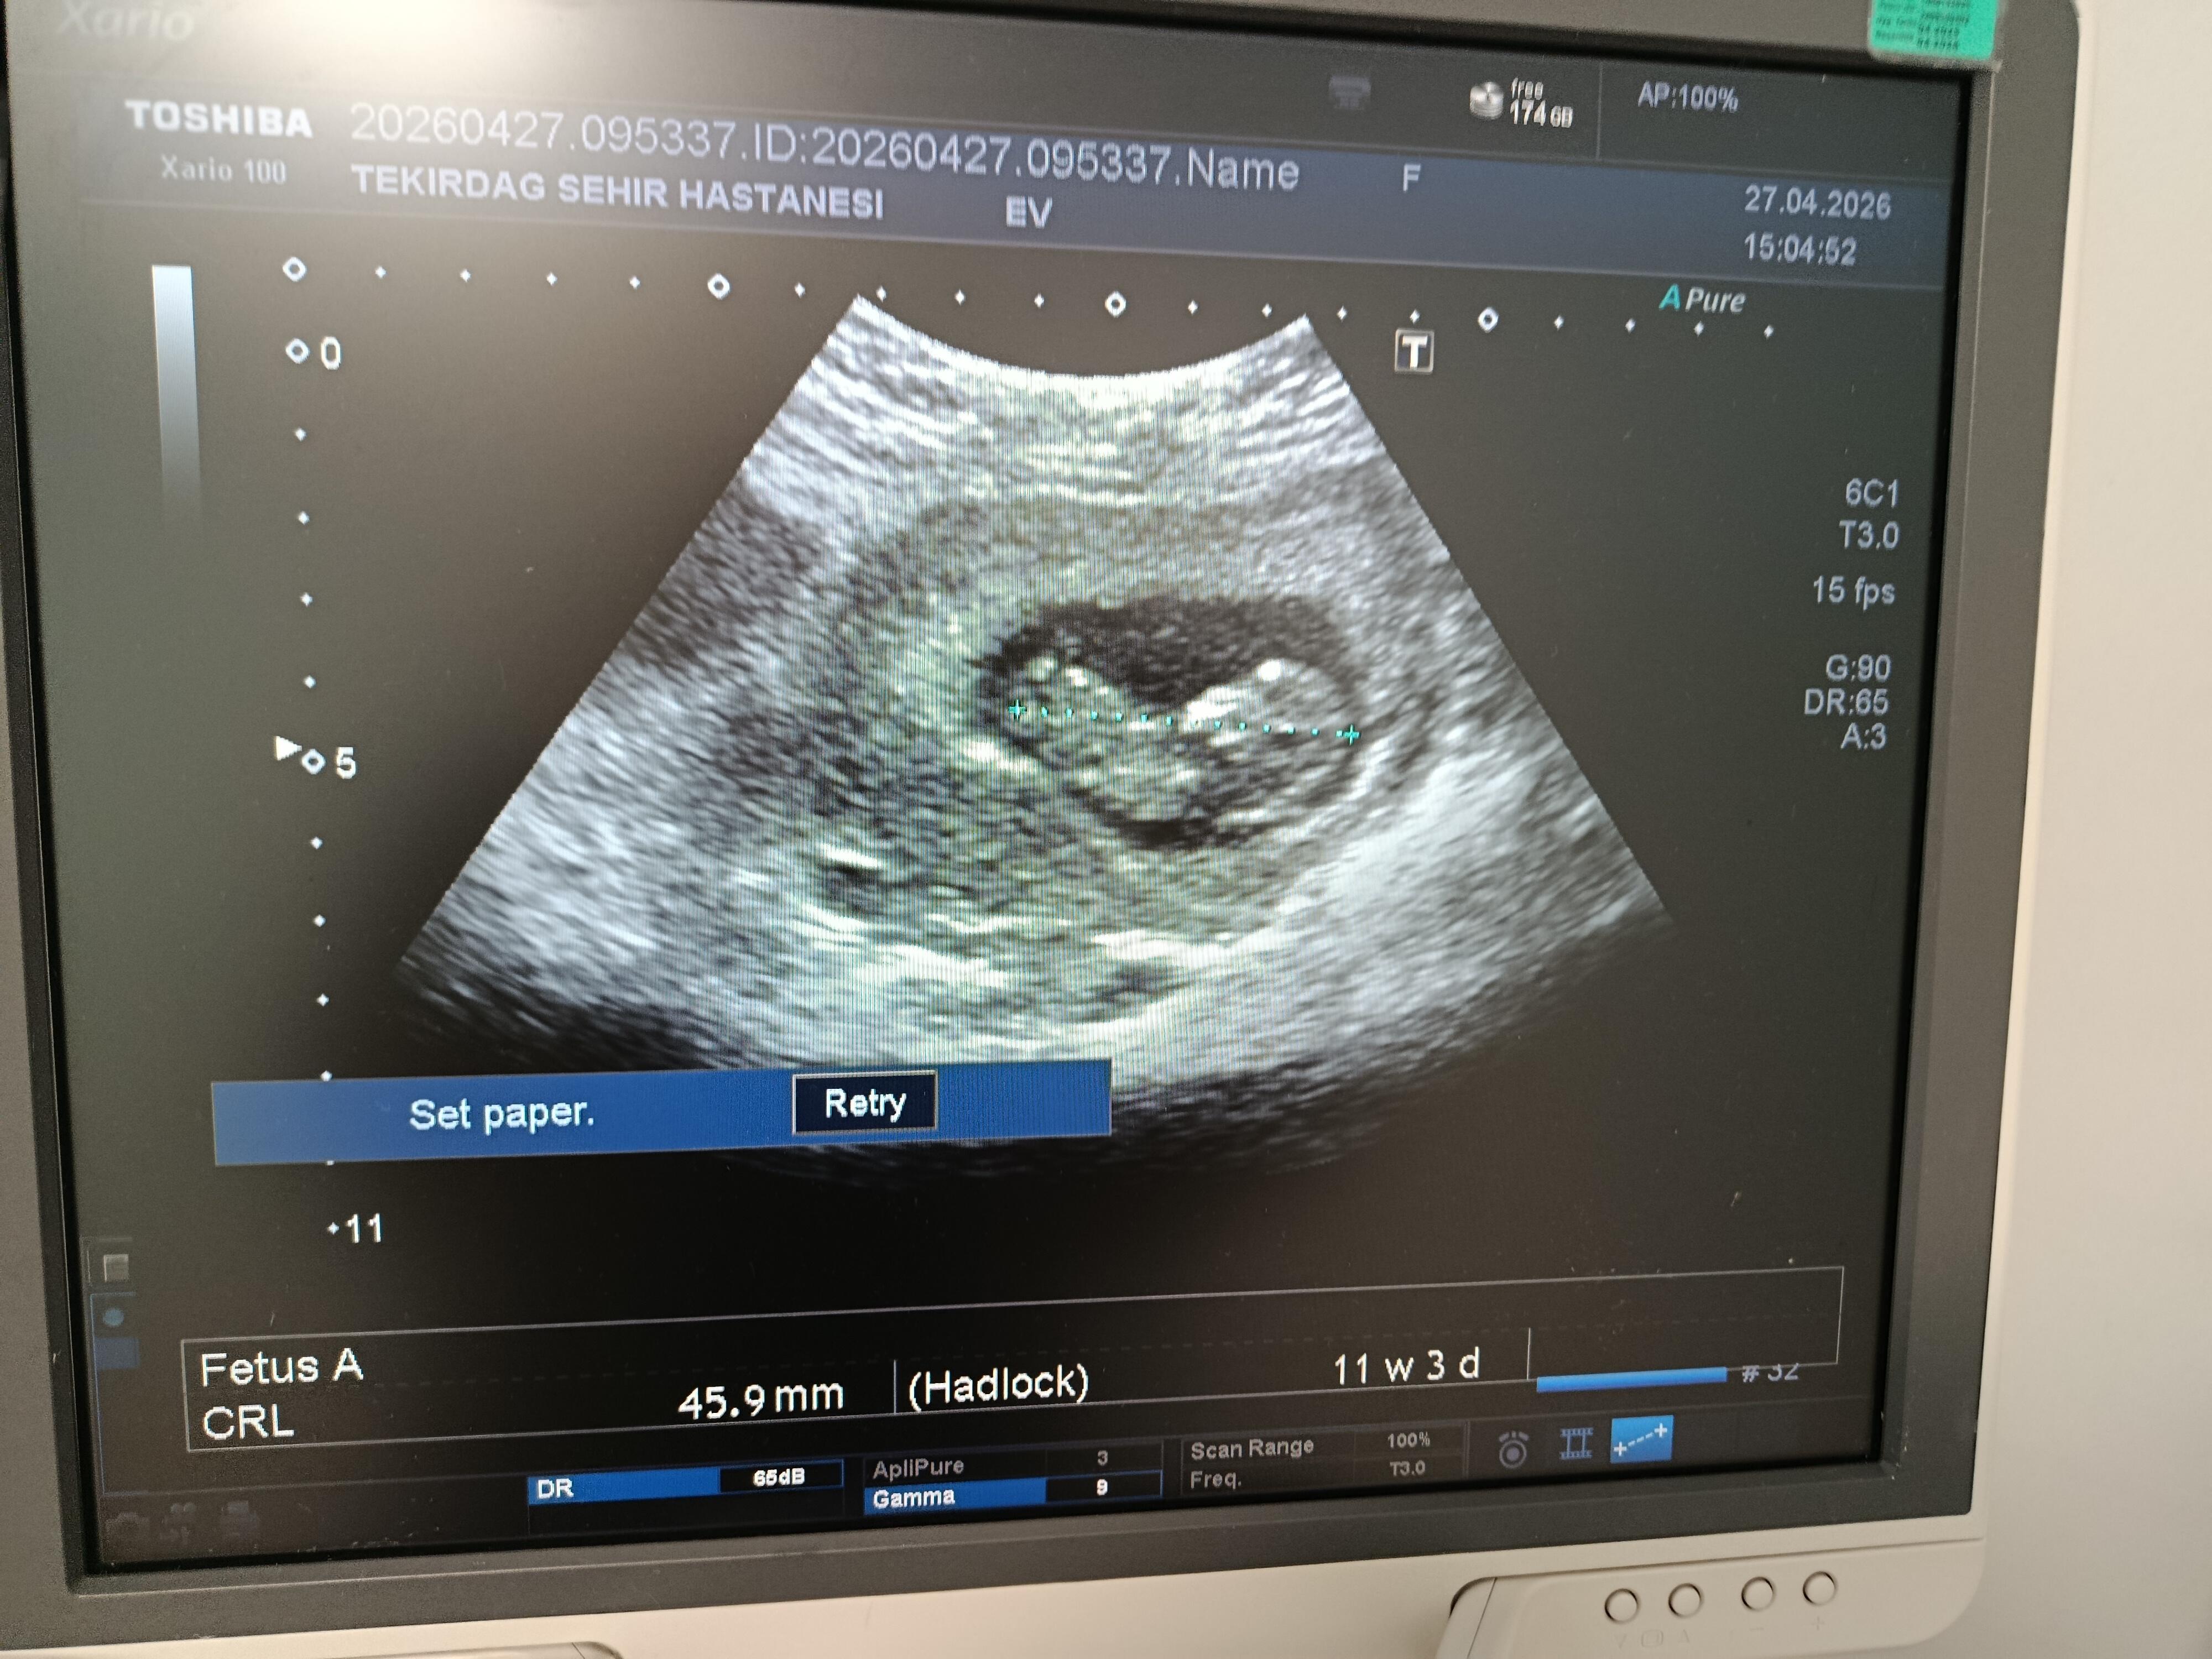

yeni fotografla geldim cinsiyet tahmini alabilirmiyim

Kızz yüksek oranla %80 felan

Prenses gibi canım bacak arasından bir çıkıntı yok

Bu bir prenses gibi duruyor canim